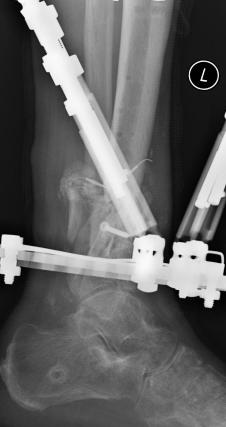

Postoperative (13th) images of left ankle

The image(s) displayed here were created following Liam's 13th surgery which was performed by Dr. Saunders. After a few hiccups getting

the surgery scheduled, Liam spent most of the September 13th afternoon in his 13th surgery. ;-) The surgery lasted about 5 hours and according

to the doctor, it was a good surgery. The 1st photo shows the new frame bracing that holds Liam's ankle together. The next series of photos show

various angles of the ankle and the rods that go from the frame into and through the left ankle. There was some concern that the swelling would

burst and allow for infection. Looks like we are now past that concern. Liam is still on antibiotics to ward of potential infection. The flesh

images show how the skin reacts to having the leg adjusted by the brace. The doctor has had to cut the skin to allow the rods to move freely.